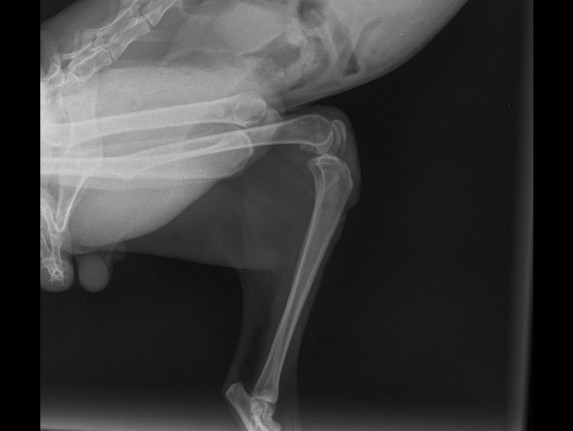

| История болезней/травм | 28.12.2025 - скальп кожи с бедра левой лапы и укол в колено. Где-то зацепился и потянул. Месяц так проходил, никто не помогал. Благодаря морозу заражения сильного не было. Обращение в ветклинику "КОТоПЁС": осмотр, стрижка, чистка раны солевым раствором, наложение повязки с лекарством (септо-спрей, бранолинд) и антибиотики (Кладакса, Марфлоксин) с обезболивающим, рентген. 29.12.2025 - Обращение в ветклинику "КОТоПЁС": осмотр, чистка раны солевым раствором, наложение повязки с лекарством (септо-спрей, бранолинд) и антибиотики с обезболивающим. 30.12.2026 - антибиотики. 31.12.2025 - Обращение в ветклинику "Эмили": чистка раны солевым раствором, наложение повязки с лекарством (септо-спрей, бранолинд) и антибиотики. 01.01.2026 - антибиотики. 02.01.2026 - чистка раны солевым раствором, наложение повязки с лекарством (септо-спрей, бранолинд) и антибиотики. 03.01.2026 - антибиотики. 04.01.2026 - Обращение в ветклинику "КОТоПЁС": осмотр, чистка раны солевым раствором, наложение повязки с лекарством (септо-спрей, бранолинд) и антибиотики, рентген. 05.01.2026 - антибиотики. 06.01.2026 - чистка раны солевым раствором, наложение повязки с лекарством (септо-спрей, бранолинд) и антибиотики. 07.01.2026 - антибиотики. 08.01.2026 - чистка раны солевым раствором, наложение повязки с лекарством (септо-спрей, бранолинд) и антибиотики. 10.01.2026 - Обращение в ветклинику "КОТоПЁС": осмотр, чистка раны солевым раствором, наложение повязки с лекарством (септо-спрей, бранолинд) и антибиотики. 11.01.2026 - антибиотики, глистогонка. 12.01.2026 - чистка раны солевым раствором, наложение повязки с лекарством (септо-спрей, бранолинд) и антибиотики. 13.01.2026 - чистка раны солевым раствором, наложение повязки с лекарством (септо-спрей, бранолинд) и антибиотики. 14.01.2026 - антибиотики. 15.01.2026 - антибиотики. 16.01.2026 - чистка раны солевым раствором, наложение повязки с лекарством (септо-спрей, бранолинд) и антибиотики. 17.01.2026 - антибиотики. 18.01.2026 - антибиотики. 19.01.2026 - чистка раны солевым раствором, наложение повязки с лекарством (септо-спрей, бранолинд) и антибиотики. 20.01.2026 - чистка раны солевым раствором, наложение повязки с лекарством (септо-спрей, Повязка мазевая Исполнение-Д4 50х70) и антибиотики. 23.01.2026 - чистка раны солевым раствором, наложение повязки с лекарством (септо-спрей, Повязка мазевая Исполнение-Д4 50х70). 26.01.2026 - чистка раны солевым раствором, наложение повязки с лекарством (септо-спрей, Повязка мазевая Исполнение-Д4 50х70). 29.01.2026 - чистка раны солевым раствором, наложение повязки с лекарством (септо-спрей, Повязка мазевая Исполнение-Д4 50х70) и антибиотики. 30.01.2026 - антибиотики. 31.01.2026 - чистка раны солевым раствором, наложение повязки с лекарством (септо-спрей, бранолинд) и антибиотики. 01.02.2026 - антибиотики. 02.02.2026 - чистка раны солевым раствором, наложение повязки с лекарством (септо-спрей, бранолинд) и антибиотики. 03.02.2026 - чистка раны солевым раствором, наложение повязки с лекарством (септо-спрей, бранолинд). 04.02.2026 - чистка раны солевым раствором, наложение повязки с лекарством (септо-спрей, бранолинд). 06.02.2026 - чистка раны солевым раствором, наложение повязки с лекарством (септо-спрей, ихтиоловая мазь). 07.02.2026 - чистка раны солевым раствором, наложение повязки с лекарством (септо-спрей, бранолинд). 09.02.2026 - чистка раны солевым раствором, наложение повязки с лекарством (септо-спрей, бранолинд). 11.02.2026 - чистка раны солевым раствором, наложение повязки с лекарством (септо-спрей, бранолинд). 12.02.2026 - чистка раны солевым раствором, наложение повязки с лекарством (септо-спрей, бранолинд). 14.02.2026 - чистка раны солевым раствором, наложение повязки с лекарством (септо-спрей, бранолинд). 15.02.2026 - чистка раны солевым раствором, наложение повязки с лекарством (септо-спрей, Повязка мазевая Исполнение-Д4 50х70). 17.02.2026 - чистка раны солевым раствором, наложение повязки с лекарством (септо-спрей, Повязка мазевая Исполнение-Д4 50х70). 19.02.2026 - чистка раны солевым раствором, наложение повязки с лекарством (септо-спрей, Повязка мазевая Исполнение-Д4 50х70). 20.02.2026 - чистка раны солевым раствором, наложение повязки с лекарством (септо-спрей, ихтиоловая мазь). 22.02.2026 - чистка раны солевым раствором, наложение повязки с лекарством (септо-спрей, ихтиоловая мазь). 24.02.2026 - чистка раны солевым раствором, наложение повязки с лекарством (септо-спрей, ихтиоловая мазь). 26.02.2026 - чистка раны солевым раствором, наложение повязки с лекарством (септо-спрей, ихтиоловая мазь). 28.02.2026 - чистка раны солевым раствором, наложение повязки с лекарством (септо-спрей, ихтиоловая мазь). 02.03.2026 - чистка раны солевым раствором, наложение повязки с лекарством (септо-спрей, ихтиоловая мазь). 03.03.2026 - чистка раны солевым раствором, наложение повязки с лекарством (септо-спрей, ихтиоловая мазь). 04.03.2026 - чистка раны солевым раствором, наложение повязки с лекарством (септо-спрей, ихтиоловая мазь). 06.03.2026 - чистка раны солевым раствором, наложение повязки с лекарством (септо-спрей, ихтиоловая мазь). 07.03.2026 - чистка раны солевым раствором, наложение повязки с лекарством (септо-спрей, ихтиоловая мазь). 08.03.2026 - чистка раны солевым раствором, наложение повязки с лекарством (септо-спрей, ихтиоловая мазь). 10.03.2026 - чистка раны солевым раствором, наложение повязки с лекарством (септо-спрей, ихтиоловая мазь). 12.03.2026 - чистка раны солевым раствором, наложение повязки с лекарством (септо-спрей, ихтиоловая мазь). 14.03.2026 - чистка раны солевым раствором, наложение повязки с лекарством (йод и солевой раствор, ихтиоловая мазь). 16.03.2026 - чистка раны солевым раствором, наложение повязки с лекарством (йод и солевой раствор, ихтиоловая мазь) и антибиотики. 17.03.2026 - антибиотики. 18.03.2026 - чистка раны солевым раствором, наложение повязки с лекарством (йод и солевой раствор, ихтиоловая мазь) и антибиотики. 19.03.2026 - глистогонка "Дирофен". 20.03.2026 - чистка раны солевым раствором, наложение повязки с лекарством (йод и солевой раствор, ихтиоловая мазь) и антибиотики. 22.03.2026 - чистка раны солевым раствором, наложение повязки с лекарством (йод и солевой раствор, ихтиоловая мазь). 24.03.2026 - чистка раны солевым раствором, наложение повязки с лекарством (йод и солевой раствор, ихтиоловая мазь). 26.03.2026 - чистка раны солевым раствором, наложение повязки с лекарством (йод и солевой раствор, Повязка мазевая Исполнение-Д4 50х70) и антибиотики. 27.03.2026 - антибиотики. 28.03.2026 - чистка раны солевым раствором, наложение повязки с лекарством (йод и солевой раствор, Повязка мазевая Исполнение-Д4 50х70) и антибиотики. 29.03.2026 - антибиотик 30.03.2026 - чистка раны солевым раствором, наложение повязки с лекарством (йод и солевой раствор, Повязка мазевая Исполнение-Д4 50х70) и антибиотики. 31.03.2026 - антибиотик 01.04.2026 - чистка раны солевым раствором, наложение повязки с лекарством (йод и солевой раствор, Повязка мазевая Исполнение-Д4 50х70). 04.04.2026 - чистка раны солевым раствором, наложение повязки с лекарством (йод и солевой раствор, ихтиоловая мазь). 06.04.2026 - чистка раны солевым раствором, наложение повязки с лекарством (йод и солевой раствор, Повязка мазевая Исполнение-Д4 50х70). 08.04.2026 - чистка раны солевым раствором, наложение повязки с лекарством (йод и солевой раствор, Повязка мазевая Исполнение-Д4 50х70). 10.04.2026 - чистка раны солевым раствором, наложение повязки с лекарством (йод и солевой раствор, Повязка мазевая Исполнение-Д4 50х70). 12.04.2026 - чистка раны солевым раствором, наложение повязки с лекарством (йод и солевой раствор, Повязка мазевая Исполнение-Д4 50х70). 14.04.2026 - чистка раны солевым раствором, наложение повязки с лекарством (йод и солевой раствор, Повязка мазевая Исполнение-Д4 50х70), глистогонка "Дирофен" и антибиотик (Кладакса). Заметно перестаёт кушать. 15.04.2026 - антибиотик (Кладакса). Плохо ест сам. 16.04.2026 - чистка раны солевым раствором, наложение повязки с лекарством (йод и солевой раствор, Повязка мазевая Исполнение-Д4 50х70) и антибиотик (Кладакса). 17.04.2026 - антибиотик (Кладакса). Ест только рыбку. 18.04.2026 - чистка раны солевым раствором, наложение повязки с лекарством (йод и солевой раствор, Повязка мазевая Исполнение-Д4 50х70) и антибиотик (Кладакса). 20.04.2026 - чистка раны солевым раствором, наложение повязки с лекарством (йод и солевой раствор, Повязка мазевая Исполнение-Д4 50х70). Принудительное кормление паштетом, пьёт сам. 22.04.2026 - чистка раны солевым раствором, наложение повязки с лекарством (йод и солевой раствор, Повязка мазевая Исполнение-Д4 50х70). Принудительное кормление паштетом, пьёт сам. 24.04.2026 - чистка раны солевым раствором, наложение повязки с лекарством (йод и солевой раствор, Повязка мазевая Исполнение-Д4 50х70). Принудительное кормление паштетом, пьёт сам. 26.04.2026 - чистка раны солевым раствором, наложение повязки с лекарством (мазь стрептоцид и солевой раствор, Повязка мазевая Исполнение-Д4 50х70). Принудительное кормление паштетом и водой. 28.04.2026 - чистка раны солевым раствором, наложение повязки с лекарством (мазь стрептоцид и солевой раствор, Повязка мазевая Исполнение-Д4 50х70). Принудительное кормление паштетом и водой. 30.04.2026 - чистка раны солевым раствором, наложение повязки с лекарством (йод и солевой раствор, ихтиоловая мазь). Принудительное кормление паштетом и водой. Обращение в ветклинику "ЭМИЛИ". 01.05.2026 - Обращение в ветклинику "ЭМИЛИ" - диагноз ФИП, откачка 300 мл жидкости из брюшной полости. Капельница и приём Коронакэт. 02.05.2026 - смерть. |